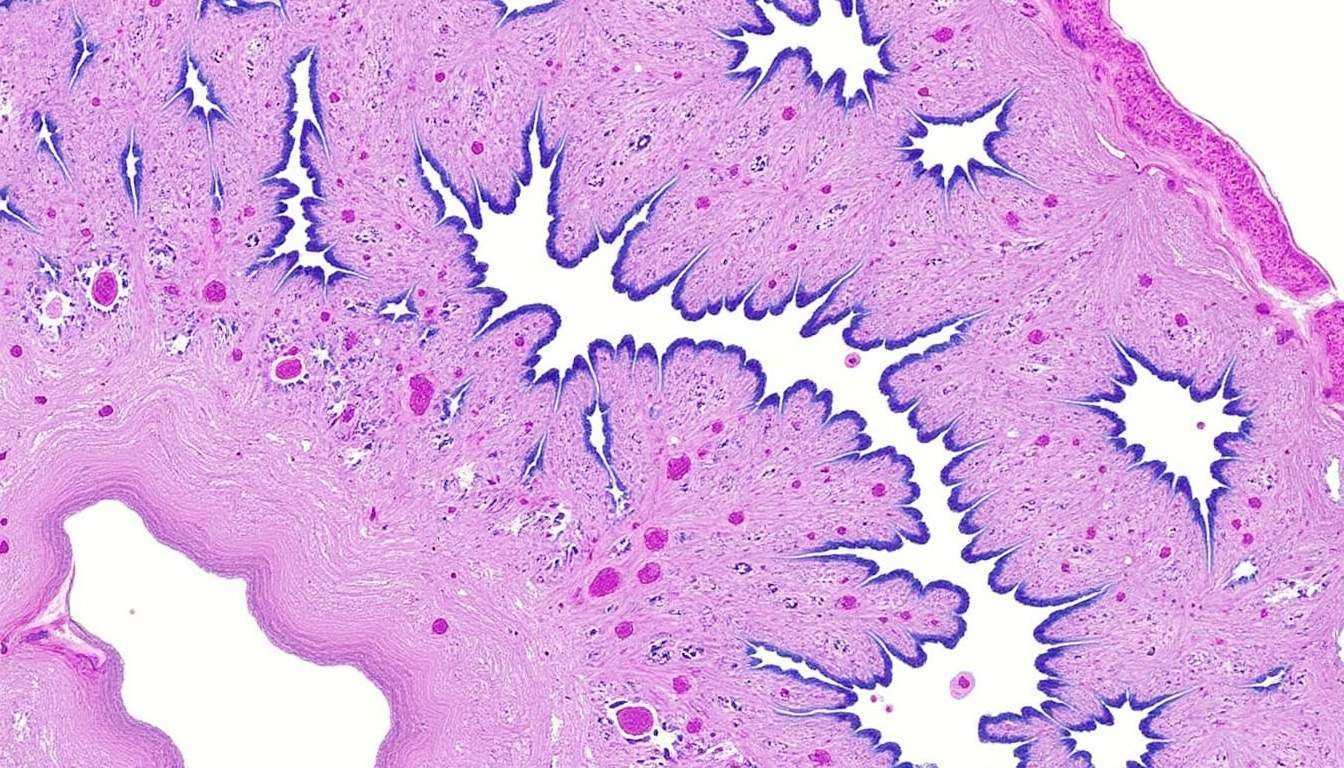

L’outil AIM-NASH est un système basé sur l’intelligence artificielle qui emploie un modèle d’apprentissage automatique. Ce modèle a été formé sur plus de 100 000 annotations provenant de 59 pathologistes ayant étudié plus de 5 000 biopsies hépatiques au cours de neuf grands essais cliniques. Grâce à cette base de données riche, AIM-NASH est capable de fournir des lectures plus fiables des biopsies, garantissant ainsi des évaluations précises de l’activité de la MASH.

Les biopsies hépatiques sont souvent considérées comme la norme d’or pour démontrer l’efficacité de nouveaux traitements. Cependant, la variabilité élevée observée dans les essais cliniques de MASH représente un défi majeur. Les spécialistes qui examinent les échantillons de biopsie ne parviennent pas toujours à s’accorder sur la gravité de l’inflammation ou des cicatrices. C’est là qu’intervient AIM-NASH, visant à réduire cette variabilité.